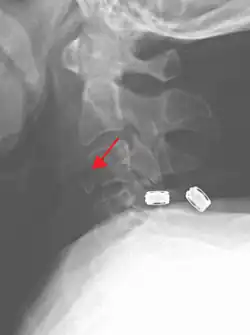

On CT scan or X-ray, a cervical fracture may be directly visualized. In addition, indirect signs of injury by the vertebral column are incongruities of the vertebral lines,[7] and/or increased thickness of the prevertebral space:[8]

-

X-ray of normal congruous vertebral lines -

![CT scan of normal congruous vertebral lines[7]](./_assets_/Vertebral_lines.png)

![CT scan with upper limits of the thickness of the prevertebral space at different levels[8]](./_assets_/CT_of_prevertebral_space.jpg)